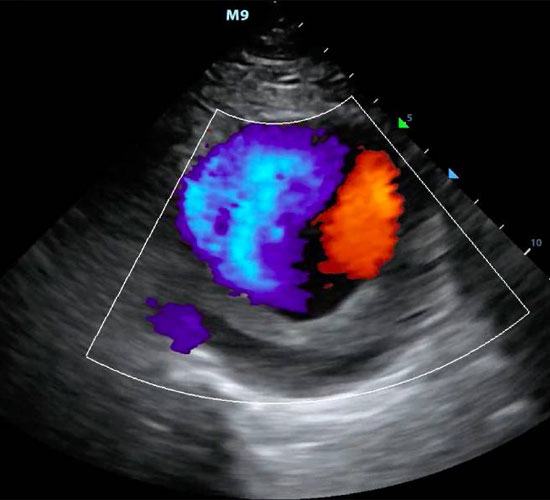

Color Doppler Test:

Color Doppler is a type of ultrasound imaging that uses color to show the direction and velocity of blood flow. It is a non-invasive and painless test that is often used to diagnose and monitor a variety of conditions, including:

Color Doppler works by sending high-frequency sound waves (ultrasound) into the body. The sound waves bounce off of blood cells and other tissues, and the echoes are returned to the transducer. A computer then analyzes the echoes to create an image of the blood vessels and blood flow.

The direction of blood flow is represented by different colors. Red represents blood flowing towards the transducer, and blue represents blood flowing away from the transducer. The velocity of blood flow is also represented by color, with brighter colors indicating faster flow.